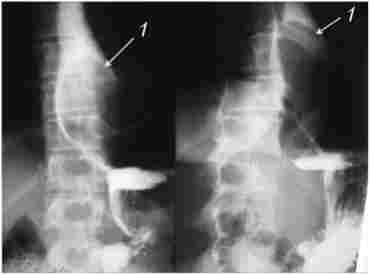

при рентгенологічному дослідженні внутріпросветние пухлини представляються у вигляді локального потовщення однієї з складок (на ранній стадії розвитку) або округлого дефекту наповнення на широкій основі або на ніжці. Обриси його різкі, іноді мелковолністие. Перистальтика не порушена, затримка контрастної маси буває лише при великих розмірах новоутворення або при локалізації його в черевній частині стравоходу над кардіальної частиною шлунка (рис. 10.1).

Рентгенограма стравоходу з лейоміомою в його середньої третини

Мал. 10.1. Рентгенограма стравоходу з лейоміомою в його середньої третини

При ковтанні освіту зміщується разом зі стінкою стравоходу в проксимальному напрямку.

При внутрістеночних пухлинах складки слизової оболонки збережені, вони можуть лише огинати пухлину, також вони зазвичай звужені або сплощені. Сама пухлина може виявлятися по крайовій дефекту наповнення з рівними контурами. При великих пухлинах спостерігається веретеноподібне розширення верхніх відділів стравоходу.